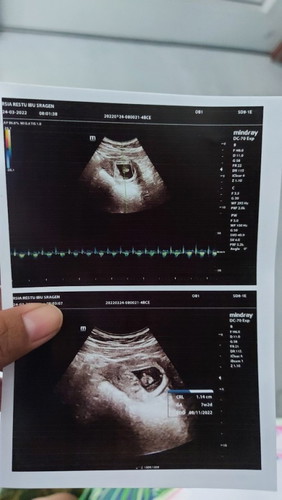

Saya hamil 7 minggu lebih dan jalan 8 minggu kemarin sempet keluar darah dan langsung di bawa ke Rs, di cek dokter dan itu hasil usg bayi baik" saja dan perkembangan juga sesuai dengan usianya, pertanyaan saya setelah minum obat dan setelah keluar darah mual munta sudah lagi berkurang banyak, nafsu makan juga mulai sedikit bertambah, itu kenapa ya bunda? Apakah berbahaya?#seriusnanya #bantusharing #ingintahu #pleasehelp #firstbaby #firstmom